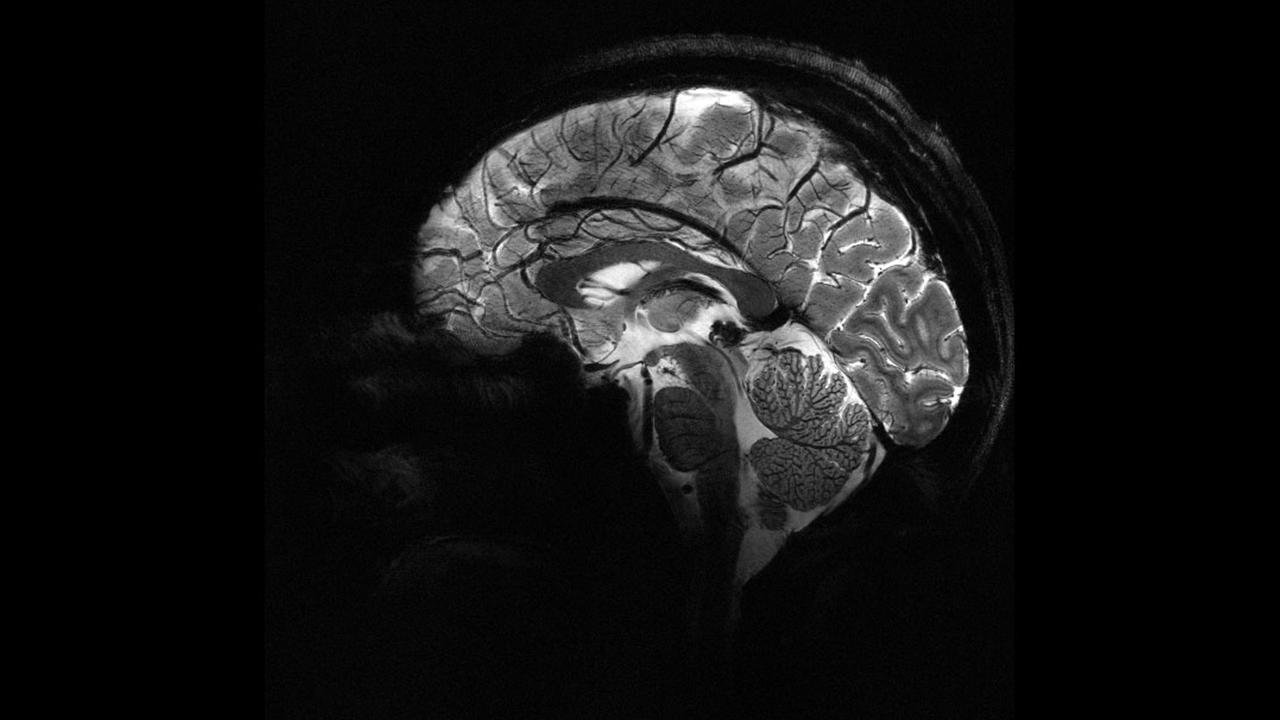

Deney sırasında beynin ön ve arka kısımlarında yer alan frontal ve paryetal bölgelere elektrik akımı uygulandı. Bu iki bölge aynı anda uyarıldığında, katılımcıların daha fazla para paylaştığı gözlemlendi.

Bu çalışma, katılımcıların para paylaşma oyunu sırasında beyin aktivitelerinin izlendiği önceki bir araştırmaya dayanıyor. Önceki çalışmada, daha fazla para paylaşıldığında beynin karar verme ve empati bölgelerinin aynı frekansta “iletişim kurduğu” tespit edilmişti. Yeni deneyle birlikte, dışarıdan müdahale ile bu bölgeler arasındaki iletişimin tetiklenebileceği ve insanların daha özverili kararlara yönlendirilebileceği kanıtlanmış oldu.

Araştırma ekibinden Dr. Jie Hu, çalışmanın en yeni yanının neden-sonuç ilişkisini ortaya koyması olduğunu söyledi. Hu, hedeflenmiş ve cerrahi müdahale gerektirmeyen bir stimülasyonla belirli bir beyin ağındaki iletişimin değiştirilmesinin, insanların kendi çıkarları ile başkalarının çıkarları arasındaki dengeyi nasıl kurduklarını doğrudan etkilediğini vurguladı.